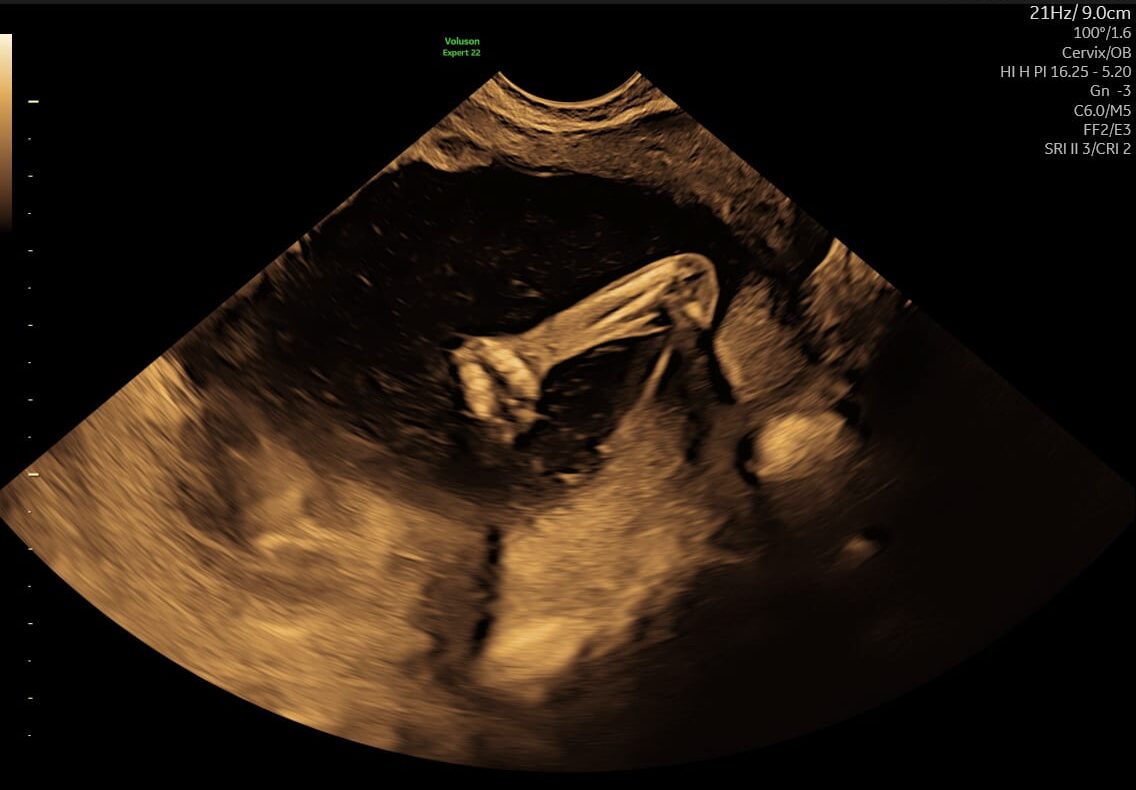

Ved en tryghedsscanning fra uge 14+0 vurderer vi blandt andet:

- moderkagens placering

Vi vurderer bl.a. hjerteaktivitet, bevægelse, fostervandsmængde, moderkagens placering og generelle trivselstegn.